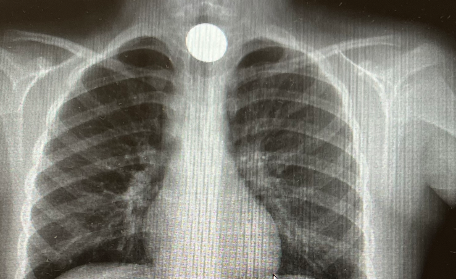

Se reinterroga a la niña, que acaba confesando la ingesta de una moneda de 2 euros por error, al estar jugando con ella. En ese momento, se decide realizar una radiografía de tórax, donde se visualiza una imagen radiopaca compatible, en la región anterior del mediastino, a nivel del tercio proximal del esófago.

Atragantamiento tras ingesta accidental de una moneda.